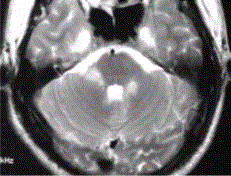

问题 患者男,35岁,肢体无力半年。头部MRI显示如下图。 患者的下一步治疗包括

选项 A.免疫抑制剂及激素 B.降颅压 C.抗炎 D.抗血栓 E.无须特殊治疗

答案 A